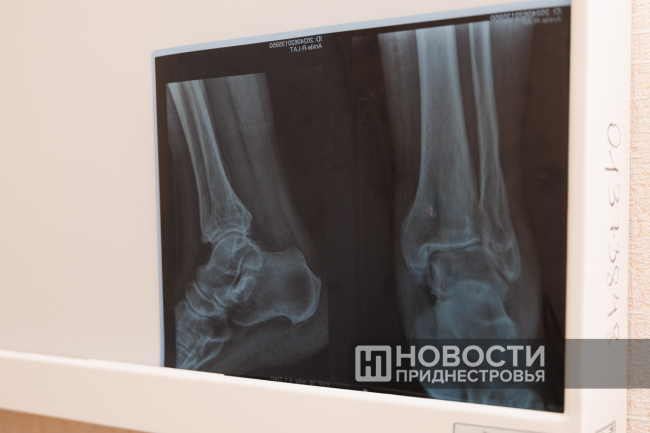

Через два месяца, когда пациенту был назначен контрольный рентгеновский снимок, он не просто пришёл в РКБ без костылей или трости – он приехал на велосипеде. В тот момент медики поняли, что операция прошла успешно.

Также при личном участии Кристиана Осадчего в РКБ начали проводить остеосинтез длинных трубчатых костей. Это хирургическая операция по сопоставлению и жёсткой фиксации костных отломков с помощью металлических конструкций. Была внедрена и артроскопия при пластике передней крестообразной связки. До этого такие сложные операции в Приднестровье не проводились. Применение врачом современных технологий позволяет сократить сроки лечения и реабилитации пациентов, ускорить восстановление их трудоспособности.